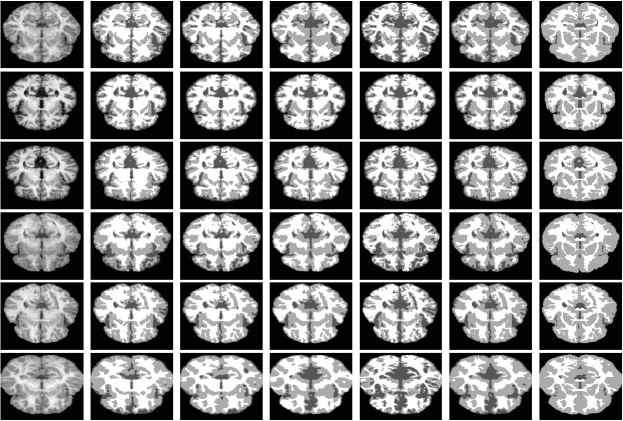

We thirdly apply the proposed three phase level set model to segment two MR brain images which are corrupted by severe intensity inhomogeneities and two selected natural images from MSRCORID database [32], namely, 164_6484 and 112_1204. The first two images are widely used to evaluate multiple phase active contour models in the literature and the last two images are selected because three kind of objects are contained which are suitable for three phase segmentation. From the results given in Fig. 5, we can see that the estimated biases are smooth and the corrected images are much more homogeneous. Moreover, the extracted objects are coincided with the images.

Orig w/ Init Bias Corrected Seg1 Seg2 Seg3

4.2 Evaluation on pubic image repositories

In this subsection, we evaluate effectiveness of the proposed model quantitatively on one simulated MR dataset and one real MR image dataset. The first one consists of 9 cases of MR images with three different levels of noise and intensity inhomogeneity, respectively. Resolutions of the images are with 1 mm in-plane pixel size and 1 mm slice thickness. For more information about the dataset, interested readers are referred to the website http://brainweb.bic.mni.mcgill.ca/brainweb/ and the reference [33]. To construct a much more challenging dataset for segmentation methods, three more levels of non-linear intensity inhomogeneities are added to the original image with noises. Therefore, there are totally 18 image cases for the first image dataset. The second image set is known worldwide as the Internet Brain Segmentation Repository (IBSR) which contains 18 cases of T1-weighted brain MR image cases with skull-removed masks and manually-guided expert segmentation results. Resolutions of the images are all . Interested readers are referred to https://www.nitrc.org/projects/ibsr for detail. Note that for each image case, the segmentation task is to extract white matter (WM), gray matter (GM), and cerebrospinal fluid (CSF) from the background. As intensities of the background are all zero for the images, two level set functions are used to partition the images into three regions that is and . To compare performance of the proposed model with state-of-the-art models like CV, LIC, and LINC on these image datasets, we first extend the comparable models to three phase (matlab codes will be released on our personal homepage if this paper got published). We then define membership functions , , and to represent WM, GM, and CSF, respectively. For a fair comparison, we first extend comparison models to three phase and then use the same parameter set and the same strategy to initialize the level set functions for all the comparison models. The initialization strategy is that areas separated by a predefined threshold are adopted to initialize by considering the areas as inside and outside of the zero level contour. Areas separated by another predefined threshold are adopted to initialize the level set function . The thresholds are adaptively defined as 0.8 and 0.3 times of maximal intensity of pending to be segmented images. We have to point out that the proposed model is robust to initialization which will be discussed in section 5.3. Note that we applied the proposed model and comparable state-of-the-art models only on image slices that really contain WM, GM, and CSF.

4.2.1 Qualitative comparison

Segmentation results of the proposed model with three state-of-the-art level set models, i.e., CV, LIC, and LINC, and the global clustering based MICO on the -th slice of selected brainweb cases and the -th slice of selected IBSR image cases are given in Fig. 8 and Fig. 10. The corresponding bias estimation and correction results are given in Fig. 9 and Fig. 11, respectively. The reason we select these image is that they are the most noisy and biased and they are therefore challengeable. It can be seen that 1) the proposed model is much more robust to noises and bias fields and 2) segmentation results of the proposed model are much more close to corresponding ground truth. Due to potential relatedness of the proposed model to MICO, it is necessary to compare them qualitatively and quantitatively, beside describing theoretical differences as given in Remarks 8-10. It can be obviously seen that 1) MICO is sensitive to noise, especially as shown for the first two images of Fig. 8 with 9% and 6% noises to the brightest tissue and 2) MICO prefers to provide high biases at image centres which can be seen from Fig. 10 and especially for the first image in Fig. 8 with no intensity biases actually. But bias fields estimated by the proposed model are much more matching with the actual situation and the bias estimated is almost a constant for the first image in Fig. 8 which is not corrupted by inhomogeneities in fact. Quantitative evaluation will be given in section 4.2.2.

Orig CV LIC LINC MICO IEOPF GT